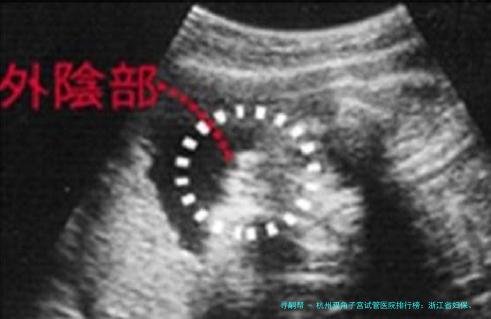

简介:专注于女性不孕不育症的超声诊断与治疗,尤为擅长使用三维超声等影像技术评价双角子宫等畸形样子,为移植提供准确导航。临床操作技术精湛。